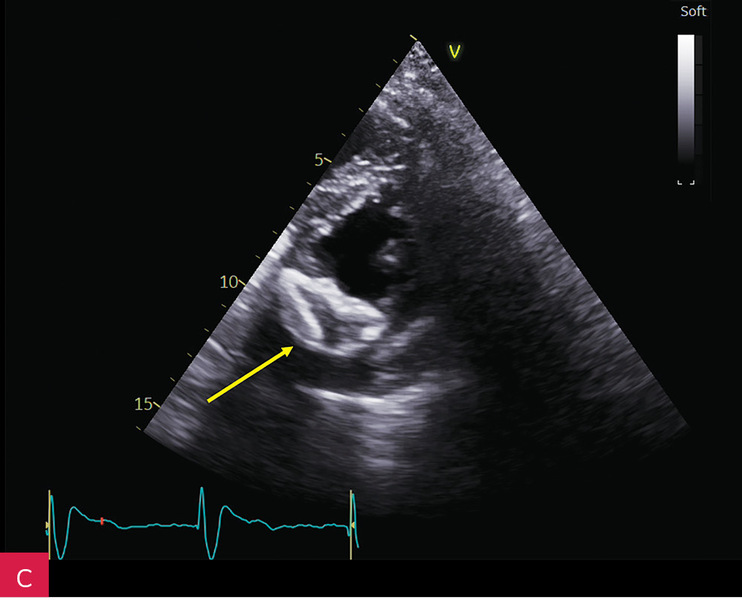

Rycina 9A-C. Kontrolne badanie echokardiograficzne przezklatkowe (TTE) po 5 miesiącach od rozpoznania uwidoczniło porównywalne wymiary zmiany guzowatej jak w badaniu wyjściowym (A), brak progresji zwężenia zastawki mitralnej (B), charakterystyczny obraz uwapnionej otoczki z bezechowym rdzeniem wewnętrznym (C)

Biorąc pod uwagę stabilny obraz kliniczny po zastosowaniu leczenia farmakologicznego i zabezpieczeniu chorej stałą stymulacją serca oraz brak istotnej wady zastawki mitralnej, pacjentkę zakwalifikowano do leczenia zachowawczego i obserwacji z regularną oceną echokardiograficzną (ryc. 9).